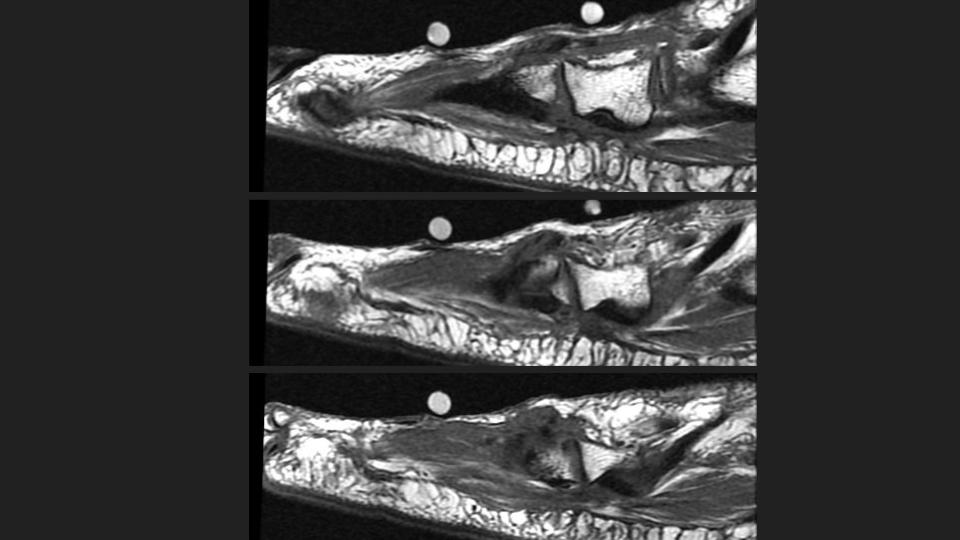

Figure 4 for case peroneus tertius ( RID2915 )

Figure 4

Area of pain indicated by markers surrounds the insertion of the Peroneus Tertius tendon onto the base of the 5th and likely also 4th dorsal MT base. The tendon is thickened with intrasubstance intermediate T1 and bright T1 signal. This is the insertional tendinosis of the peroneus tertius, with probable superimposed partial intrasubstance insertional tear suggested in the Sag fat sat images. The reference does not say much about the insertion, but includes some anatomic references that indicate variation in the insertion site at the 5th and sometimes 4th and 5th MT base. Reference article.